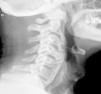

The authors present the case of a 76-year-old man previously diagnosed with diffuse idiopathic skeletal hyperostosis who presented with severe progressive myelopathy. A magnetic resonance imaging of his cervical spine revealed a retro-odontoid predural mass, which caused a severe compression of the cervical spinal cord. The patient underwent a posterior laminectomy of the atlas and an occipitocervical fusion. After surgery, the pseudotumor was considerably smaller and the neurological symptoms improved.